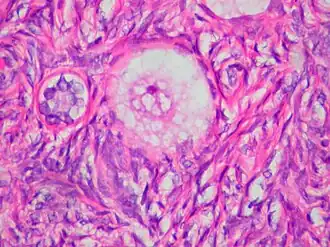

![]() Corte de un Ovocito en el centro de un folículo primario. | ||

El ovocito muestra cambios citológicos en su transición desde un folículo primordial hasta un folículo ovárico desarrollado.[3]

Posteriormente, las células parietales se diferencian hacia células de la granulosa (CG), que proliferan hasta formar una capa de células cuboidales que circundarán totalmente el ovocito, formando así el folículo primario.[8]